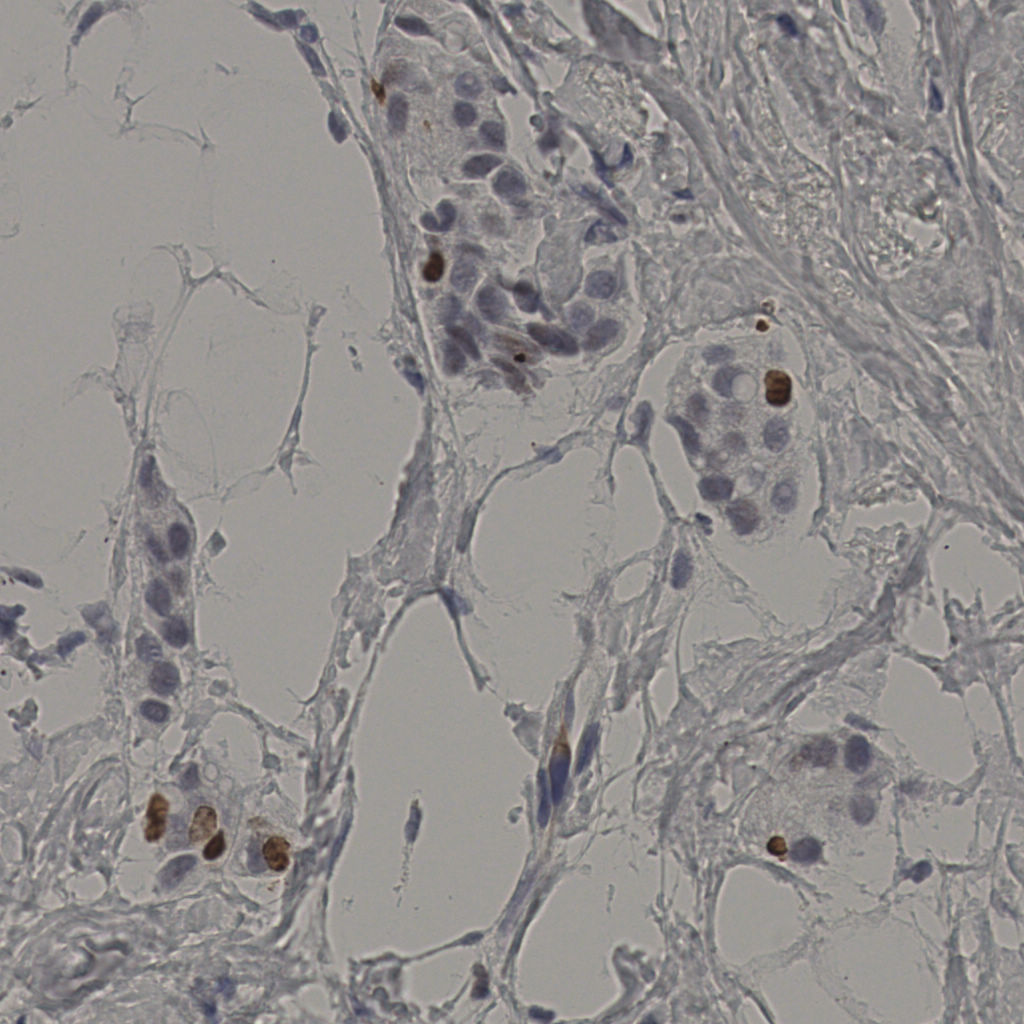

5.31%

Ki67 指数

阴 19502

阳 1093

标记后

标记前